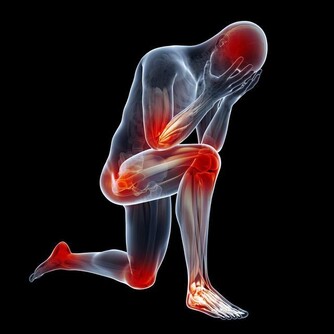

其實很多人到了晚年都是患上了各種疾病,難忍病痛的折磨,也是夠辛苦的;如果是百歲的老人,他們的子女大都已經去世,還要忍受與親人離別的痛苦,是何等的煎熬。